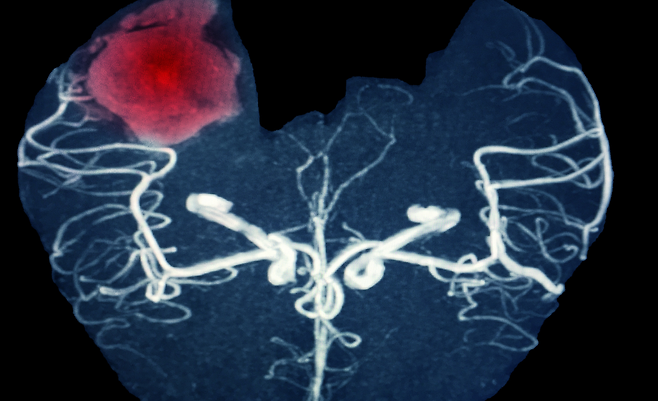

뇌출혈은 단 한 번의 발병으로도 생명을 위협하거나 심각한 후유증을 남길 수 있어 각별한 주의가 요구되고 있다. 특히 중장년층에서 발병률이 높고, 예방만이 최선의 대책으로 꼽히는 만큼 일상에서 실천할 수 있는 건강 습관이 강조되고 있다.